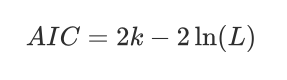

AIC的定义如下:

其中:

- ( k ) 是模型中参数的数量。

- ( L ) 是模型的最大似然估计值。

AIC的核心思想是,一个好模型应该在拟合数据(即最大化似然函数)和保持模型简洁(即参数数量较少)之间取得平衡。AIC通过惩罚模型中参数的数量来实现这一点,因为参数数量越多,( k ) 越大,AIC值也就越高。

在实际应用中,研究者会比较多个模型的AIC值:

- 一个模型的AIC值越低,表示该模型在拟合数据和保持简洁之间取得了更好的平衡。

- 当面对多个候选模型时**,AIC值最低的模型通常被认为是最合适的模型**。

AIC的一个主要优点是它提供了一种相对简单的方法来选择最佳模型,而不需要对模型的似然函数进行复杂的比较。然而,AIC也有局限性,它假设所有模型都是正确指定的,即模型的形式和分布假设都是正确的。如果模型的假设不正确,AIC可能会导致错误的模型选择。

在机器学习和统计分析中,AIC常用于模型选择,尤其是在变量选择、特征选择和决策树剪枝等场景中。通过最小化AIC,可以帮助识别对数据拟合最好且最简洁的模型。